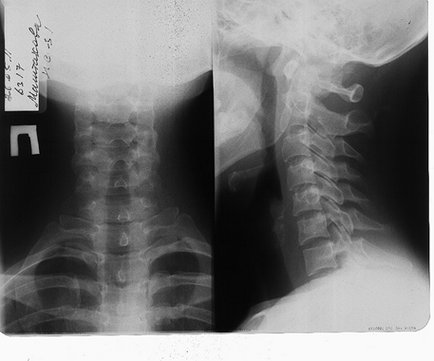

Röntgensugarak

Egy módszer, ami lehetővé teszi, hogy a bizonytalanság a nyaki gerinc, valamint a bruttó patológia (törések, csigolya elmozdulás).

A X-ray is látni a csont razrostaniya, változások fasetochnyz ízületek.